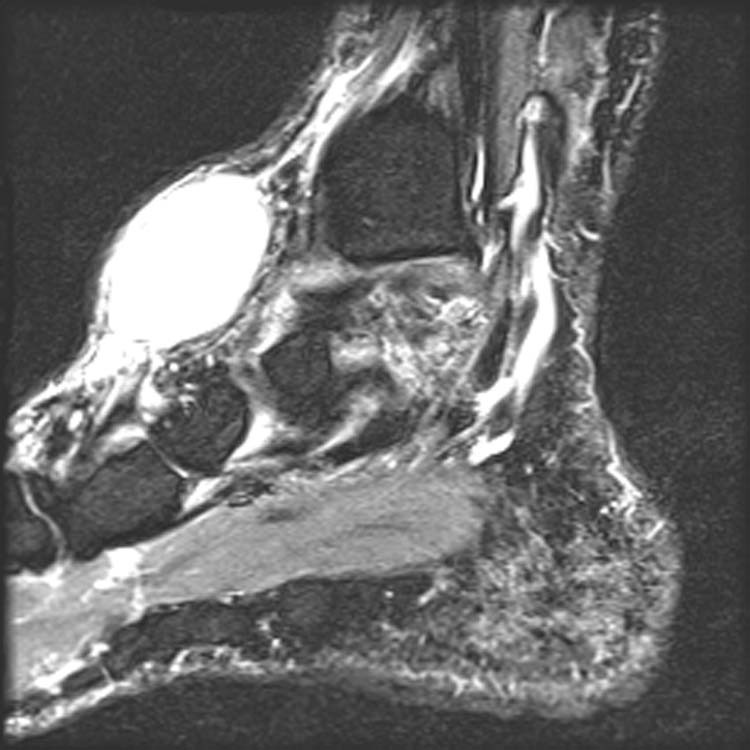

Мы сообщаем о случае 62-летнего мужчины с хронической венозной язвой в анамнезе (последние два года), страдающего ожирением, заядлого курильщика, у которого опухоль развивалась в течение трех месяцев, прогрессивно увеличиваясь в размерах на поверхности раны нижней конечности в сочетании с кожными признаками тяжелого застойного дерматита. Клиническое обследование выявило на левой нижней конечности, претибиально изъязвленную экзофитную опухоль размером 4х7 см с участками активного кровотечения и покрытую гнойными выделениями (рис. 1А и 1B). Также присутствовали серьезные признаки застойных явлений: двусторонний отек, дерматосклероз и бела атрофия кожи. Лабораторные данные показали аномальные значения маркеров воспаления. Бактериологические тесты выявили наличие золотистого стафилококка, чувствительного к широкому спектру антибиотика. УЗДС вен показало несостоятельность перфорантных вен и исключило тромбоз глубоких вен. Рентгенологическое исследование левой нижней конечности исключило вовлечение костных структур. Поскольку эта клиническая картина убедительно свидетельствовала о злокачественной опухоли, развивающейся на фоне хронической венозной язвы, была проведена биопсия с края поражения.

Следовательно, пациенту были проведены дополнительные методы визуализации: УЗИ брюшной полости, компьютерная томография грудной клетки и брюшно-тазовых органов с контрастированием.